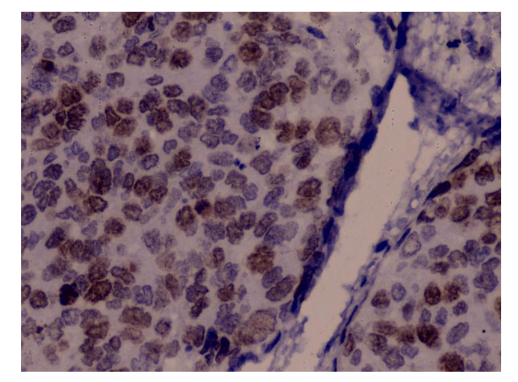

Figure 2 shows an immunohistochemical staining of cervical tissue, demonstrating strong nuclear positivity in numerous epithelial cells. The brown chromogen deposits indicate positive expression of the target biomarker Ki-67, while the background tissue is counterstained in blue with hematoxylin to visualize nuclei of negative cells. The distribution of staining is widespread, with high labeling density, consistent with a high-grade lesion showing marked proliferative or dysplastic activity.